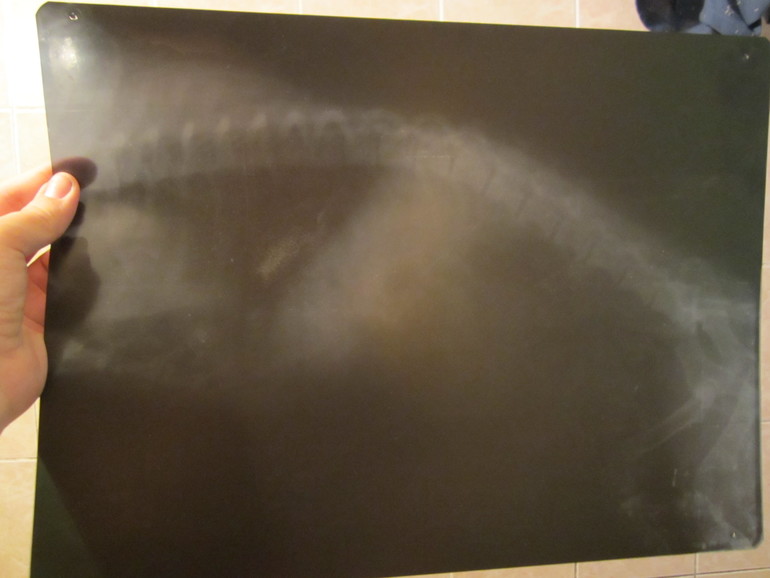

Снимки и рецепт на 1.5 тысячи! 33c64c3986d270dfd5340402646a9601.jpg 784fe7585e98cc110109ac9b5ebdfa5c.jpg 11fcd4eb2e2db72558f37dc1407cd37d.jpg 087fb9117314b14ca74bdf89e185964e.jpg

Итого: такси туда-обратно 1000рприём:350ренген:1000,(это хорошо , что успели до 22-00Если позже в 2 раза больше.и лекарства на 1.5 т.р. verysad.gifverysad.gifverysad.gifverysad.gifsmiley-cry.gif

Девочки врач сказал защемление позвоночников, сделал  обезболивающее и  сказал плавать собаке надо чаще!!!посмотрим как дальше будет.!слава богу не перелом !буду пока обезболы давать !